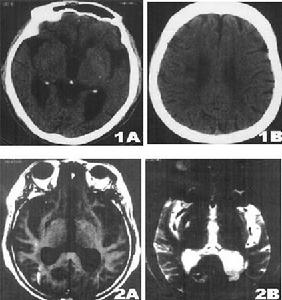

兩側半卵圓中心側腦室旁深部腦白質呈不甚對稱的長T1WI長T2WI信號,無占位效應,在T1WI圖像上呈低信號,T2圖像上呈高信號,全部病人腦室擴大,腦溝增寬,腦池擴大,表現為腦萎縮特徵。78例(89.6%)為多發性腦梗塞,9例(10.3%)為單發性腦梗塞,其中6例(6.9%)伴出血灶,男2例,女4例,其13例(14.9%),CT未發現腦梗塞,由MRI明確診斷。主要是對腦內脫髓鞘改變的範圍和腦萎縮的程度,特別是塞灶的大小,部位,腦缺氧早期診斷是否合併出血,這樣,對患者確定治療方案及預後有著深遠的意義。

影像學表現:CT表現為斑片狀及斑點狀低密度影,MRI表現為點狀及片狀長T1WI長T2WI信號,由腦深部灰質團塊萎縮,胼胝體繼發變薄,致使腦室擴大,又由於瀰漫性髓鞘脫失而有不同程度的腦萎縮,顯示腦溝增寬,腦池擴大(如圖1~4)。有高血壓及動脈硬化的病理基礎也可發生腦出血是腔隙性梗塞的直接原因。

賓斯旺格病診斷及鑑別診斷:CT,MRI的問世,為本病的生前診斷提供了影像學依據,CT表現為雙側腦室旁白質區與半卵圓中心顯示散在性或融合性低密度區,對稱或大致對稱,基底節,內囊與丘腦區可見多發性腔隙性梗塞,重者伴腦室擴大,其室管膜面多參差不齊,呈碎布狀。MRI表現:在腦室周圍白質與半卵圓中心顯示散在或融合性病變區,T1WI呈黑色,T2WI呈白色。重度與中度顯示腦室擴大,腔隙性梗塞顯影清晰,病灶數目比CT發現的多。SAE應與多發硬化,嚴重腦積水所致的室管膜水腫,CO中毒腦水腫期,腦囊蟲病腦炎型,ALZHEIMER氏病,PICK病,及其他特異性腦白質病,這些腦白質病變根據CT,MRI的表現特點,結合臨床表現60歲以上潛隱起病,逐漸加重,若具備卒中發作,高血壓,慢性進行性痴呆三大臨床特徵,綜合分析,即可做出診斷,也可隨訪複查。